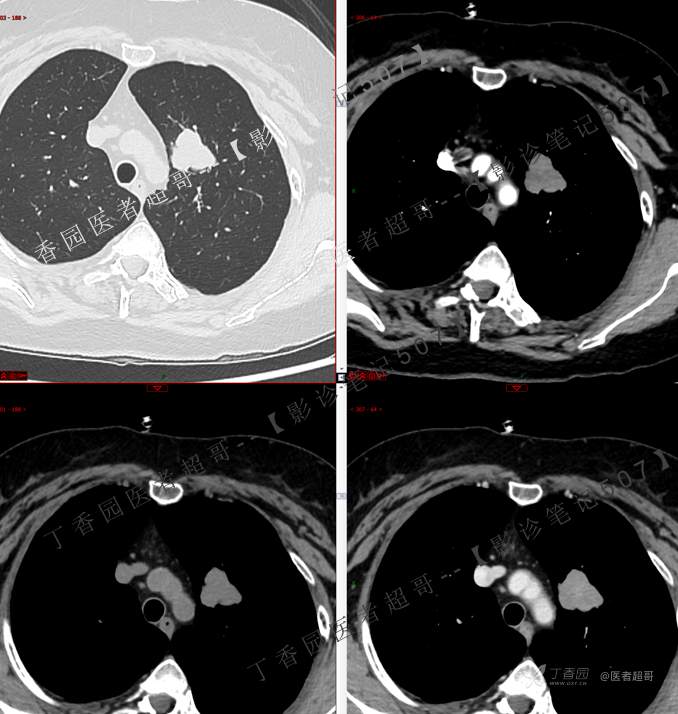

患者性别:女

患者年龄:50岁

简要病史:患者4月余前出现无明显诱因及病因出现胸痛,无咳嗽咳痰等表现。